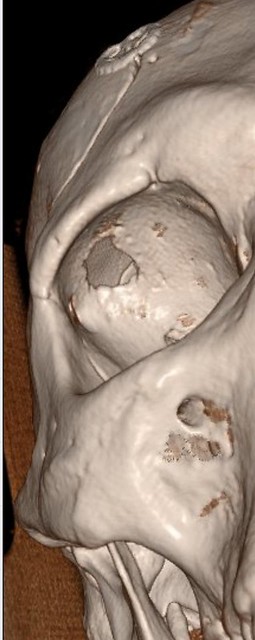

Pirms operācijas / Foto: publicitātes

Operācijas laikā neiroķirurģijas komanda veica augstas precizitātes ķirurģisku iejaukšanos - caur galvaskausu tika izveidota aptuveni 1 cm liela atvere acs dobuma sienā, ļaujot pilnībā izņemt patoloģisko veidojumu, nebojājot acs struktūras.

Padziļināti izmeklējumi atklāja ļoti retu, kalcinētu veidojumu, kas saspieda acs muskuļus un nervus, izraisot neiroloģiskos simptomus.